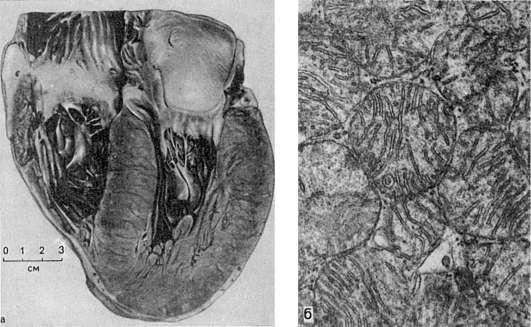

Рис.

91. Рабочая гипертрофия левого желудочка сердца:

а - внешний вид; б - гиперплазия митохондрий при гипертрофии сердца. Электронномикроскопическое исследование

Гипертрофия сердца представляет собой наиболее яркий пример компенсаторной гипертрофии и достигает наибольших степеней при врожденных и приобретенных пороках клапанов, сопровождающихся стенозом атриовентрикулярных отверстий и выносящих сосудистых трактов желудочков, при артериальной гипертензии, сужении аорты, склерозе сосудов легких и т.д. Гипертрофии подвергается преимущественно отдел миокарда, который выполняет основную работу при данных условиях нарушенного кровообращения (левый желудочек при пороках аортальных клапанов, правый - при пороке митрального клапана и т.д.). Масса сердца при этом может в 3-4 раза превышать массу нормального, достигая иногда 900-1000 г. Увеличиваются и размеры сердца (рис. 91). В основе гипертрофии миокарда лежит увеличение массы саркоплазмы кардиомиоцитов, размеров их ядер, числа и величины миофибрилл, митохондрий (см. рис. 91), т.е. гиперплазия внутриклеточных ультраструктур. При этом объем мышечных волокон увеличивается. Одновременно с гипертрофией миокарда происходит содружественная гиперплазия волокнистых структур стромы, интрамуральных сосудистых ветвей, элементов нервного аппарата сердца. Следовательно, в основе гипертрофии миокарда лежат процессы, содружественно протекающие в мышечных волокнах, строме миокарда, его сосудистой системе и интрамуральном нервном аппарате. Каждый из них представляет собой составную часть понятия «гипертрофированное сердце» и обеспечивает свое участие в развертывании и поддержании усиленной работы сердца в течение длительного, иногда многолетнего, периода.